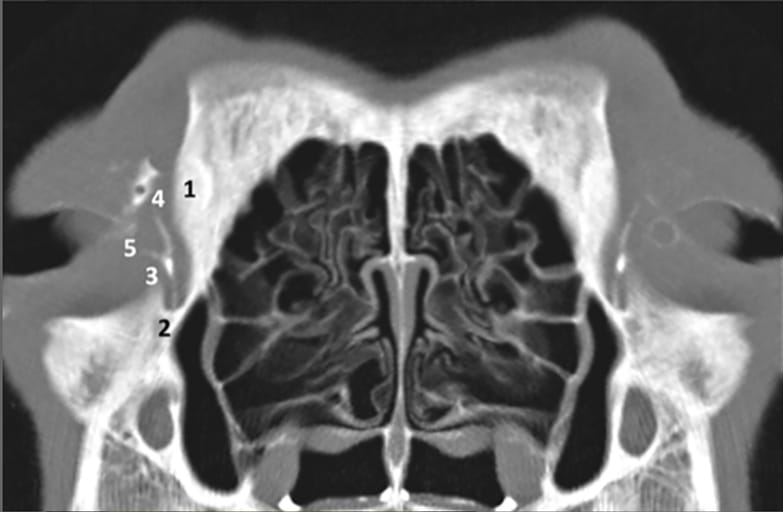

Transverse CT image (CT-Dacryocystography) of a normal mesocephalic dog at the level of the lacrimal fossa (bone window). The frontal process (1) and the lacrimal fossa (2) are easily seen. The lacrimal drainage system is filled with contrast medium (1:2 mixture of Omnipaque® 300 and methyl cellulose Adatocel®) and the upper (4) and lower (5) canaliculi, with its union in the lacrimal sac (3), are visible.